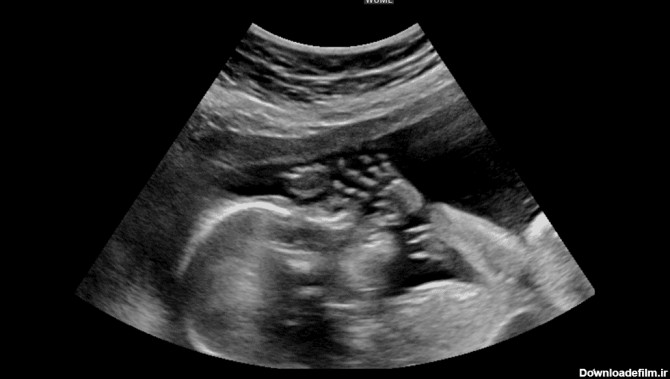

عکس جنین در غربالگری سه ماهه اول

عکس سونوگرافی سه ماهه اول - تصاویر انواع سونوگرافی جنین در هفته ها و ماه های مختلف بارداری در بهترین سونوگرافی در تهران و تهرانپارس

سونوگرافی NT در هفته های ۱۱ تا 14 بارداری انجام می شود ، در این سونوگرافی پزشک میزان مایع پشت گردن جنین و همچنین تشکیل استخوان بینی را بررسی می کند.در این بررسی احتمال اختلالات کروموزومی به خصوص سندرم داون (مونگولیسم) و مشکلات قلبی ارزیابی می شود.افزلیش NT و تاخیر در تشکیل استخوان بینی با افزلیش خطر ریست سندرم دان همراهی دارد. در کنار NT آزمایشات غربالگری سه ... | انجام کلیه امور مربوط به سونوگرافی، رادیولوژی، ماموگرافی، پانورکس و سنجش تراکم استخوان به صورت دیجیتال واقع در غرب استان تهران (شهرک اکباتان)

سونوگرافی غربالگری سه ماهه اول بارداری؛ اگرچه اکثریث زنان در بارداری نوزادسالمی دارند،امادرمواقعی این اتفاق نمی افتد.گاه ممکن است نوزاد دچار مشکل کروموزومی باشد